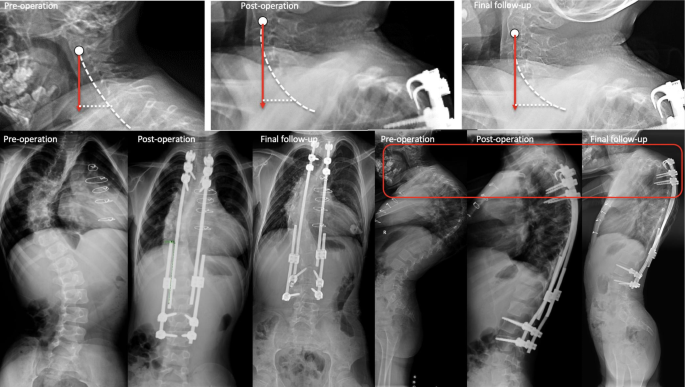

After inserting the growing rod, C2-C7 CL, T1 slope, and C2-7 SVA showed no significant change after surgery in the short term. However, in the final follow-up, C2-C7 CL, T1 slope, and C2-7 SVA increased from − 16.93 ± 10.73° to -35.45 ± 15.69°, 27.81 ± 12.95°to 41.86 ± 19.71° and 16.08 ± 11.23 mm to 23.32 ± 13.63 mm respectively (P < 0.05) (Fig. 2.) Cervical sagittal alignment changes after the growing rod surgery, as illustrated in Fig. 3.

Patients who were diagnosed with PJK had a larger C2-C7 CL and T1 slope (28.57 ± 12.43 vs. 13.35 ± 7.76, P < 0.001; 28.50 ± 11.00 vs.7.07 ± 13.50, P < 0.001). The number of growing rods and location of upper instrumented vertebrae (UIV) had no significant influence on the sagittal cervical parameters. (P > 0.05)(Fig. 4). A typical case who suffered a cervical sagittal imbalance caused by PJK is shown in Fig. 5. A case with no PJK and the sagittal cervical alignment kept balanced, as shown in Fig. 6.

During growing rod treatment, the cervical sagittal balance changes in the patient with PJK. (It is an 8-year-old male patient diagnosed with idiopathic EOS. After the 3rd distraction, scoliosis and hyperkyphosis are corrected well. In the final follow-up, he has PJK above the growing rod. Sagittal cervical alignment change: C2-C7 CL increases from 24.6° to 62.7°, T1 slope increases from 47.2° to 67.7°, and C2-C7 SVA increases from 24.3 mm to 34.2 mm.)